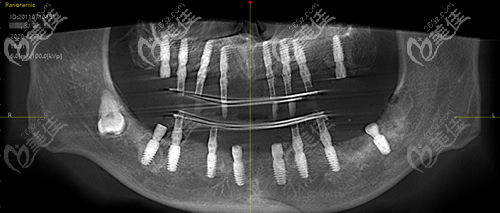

下面是術(shù)后即刻的效果,大家可以看一下:

手術(shù)當(dāng)天陳先生說(shuō)“有牙齒啃硬物的感覺(jué)真好,感謝曾院長(zhǎng)……”!

陳先生種植術(shù)后CT

對(duì)比術(shù)前術(shù)后的CT能更清晰的看到效果,所以種植牙不是大家想象的那么簡(jiǎn)單的,到專業(yè)的醫(yī)院才能更有保障。